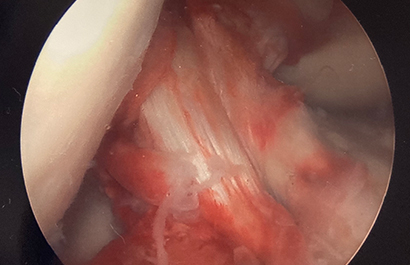

The fractures can be classified at Type 1 (minimally displaced), Type 2 (hinged with displacement of the anterior aspect), and Type 3 (completely displaced). Tibial spine fractures can be associated with other injuries including meniscal tears, bone bruising, cartilage injuries, and other non-ACL ligamentous injuries. Plain radiographs can be used to diagnose this injury, but MRI may be needed to identify concomitant injuries to the soft tissue structures. Treatment includes nonoperative management for Type 1 and some Type 2 injuries (reduction within a few millimeters of anatomic to be acceptable). Surgical fixation is indicated for irreducible Type 2 and Type 3 injuries. Surgery is usually performed arthroscopically. Fixation can be accomplished with sutures, suture anchors, or screws. Approach and fixation are often chosen based on fracture characteristics. Figure 3 shows an arthroscopic image of an avulsed tibial spine fracture. Figure 4 shows the ACL tensioned once the tibial spine is reduced while Figure 5 shows the tibial spine fragment reduced and fixed with bioabsorbable screws.

Figure 4